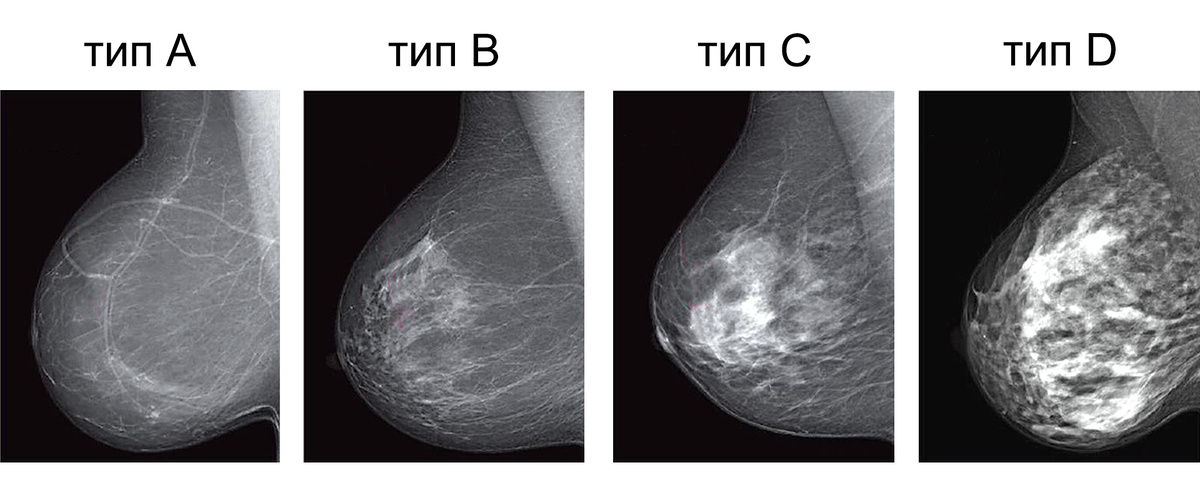

Согласно этим рекомендациям, выделяют 4 типа желез, в зависимости от их плотности.

Типы плотности молочных желез ACR

1. Тип A (около 10% всех женщин) - железа практически полностью представлена жировой тканью.

2. Тип В (около 40%) - железа состоит из жировой ткани, с разбросанными участками железистой.

3. Тип C (около 40%) - железа неоднородной плотности

4. Тип D (около 10%) - очень плотная железа, ткань которой практически полностью поглощает рентгеновское излучение.

Тип C и D принято называть железой высокой плотности, который, как мы видим, встречается у 40-50% женщин.